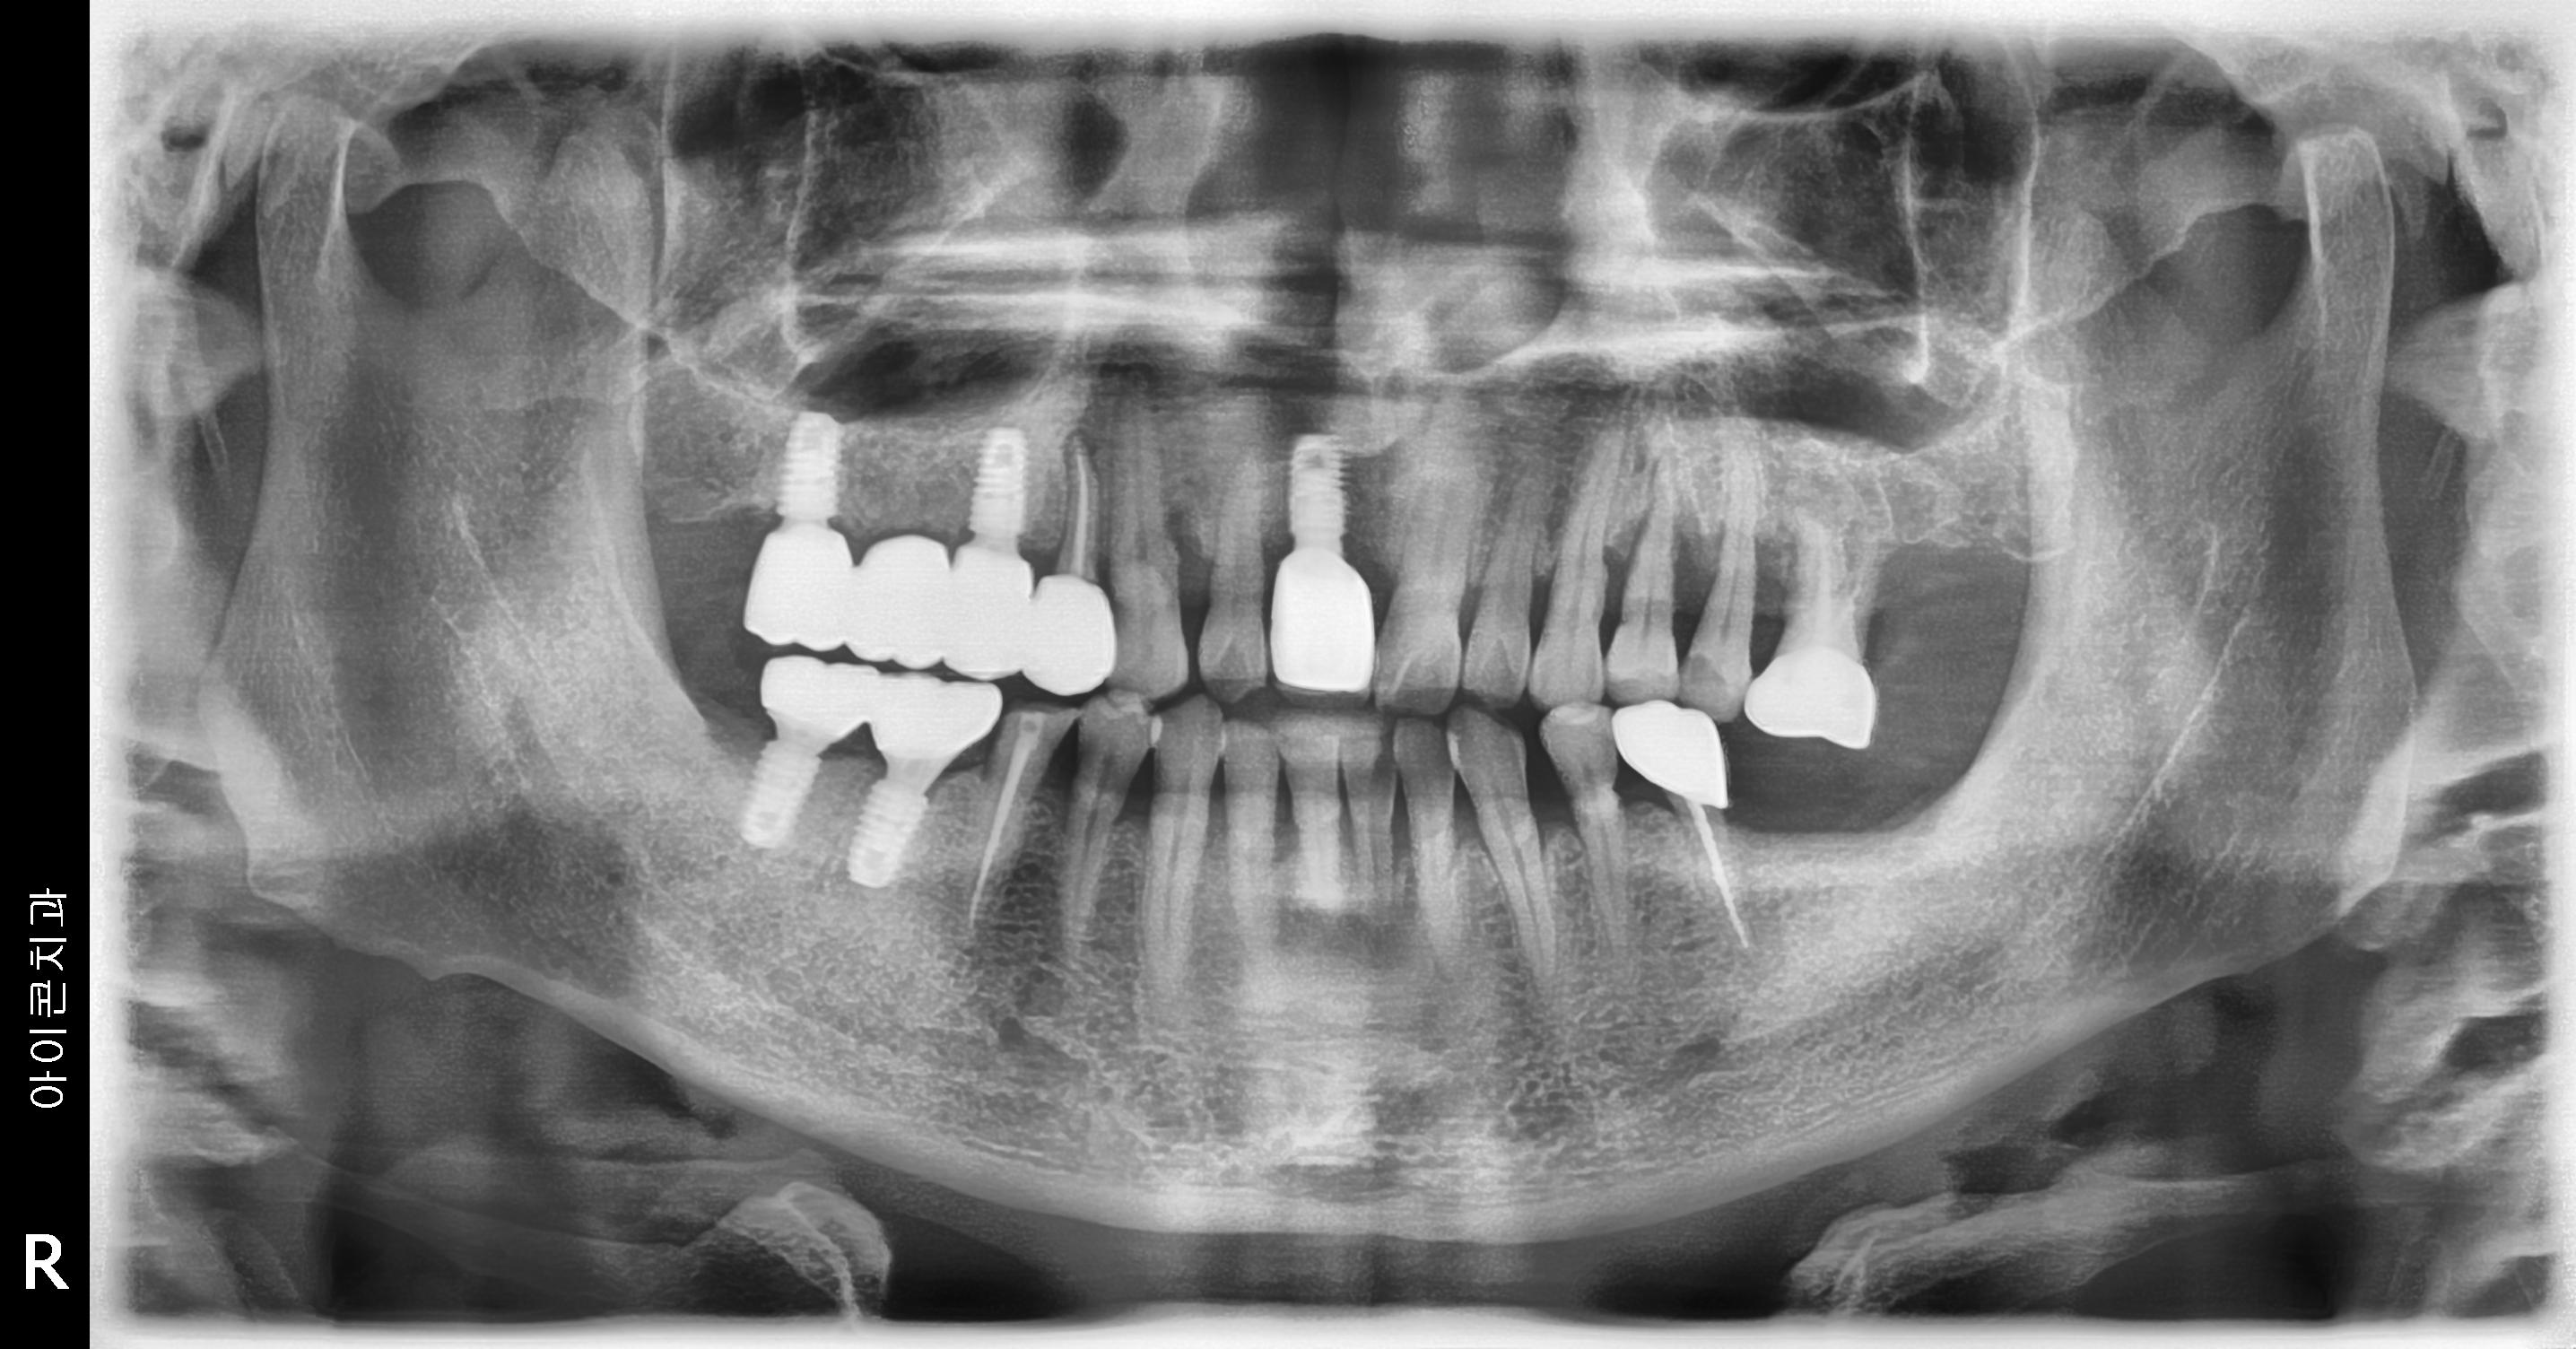

수술 전

수술 후

상하악 구치부 임플란트 식립사례

전후사진